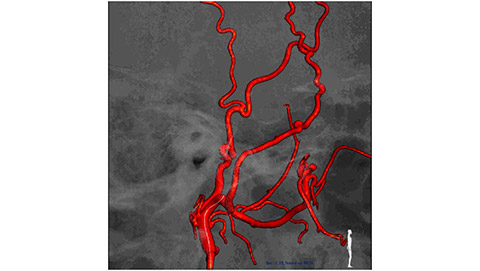

Live 3D MR/CT Roadmap fuses live 2D fluoroscopy on a pre-acquired MR or CT image, which may reveal hidden anomalies and enable real-time motion compensated navigation to support interventional procedures. Live 3D MR/CT Roadmap provides full 3D view for guidance of guidewires, catheters and coils through complex vessel and anatomical structures.

Dynamic 3D Roadmap provides a sustainable 3D roadmap to support interventional procedures. Dynamic 3D Roadmap matches the real-time 2D fluoroscopy images with the 3D-RA reconstruction of the vessel tree. It provides a 3D real-time insight of the advancement of the guide wire, catheter and coils through complex vessel structures. The Unsubtracted 3D Roadmap option reduces subtraction artifacts caused by patient breathing and movements, providing a clear roadmap during abdominal and thoracic interventions.

Live 3D Roadmap allows you to follow the advancement of guidewires, catheters and coils in real-time. It automatically adapts in real-time to changes in C-arm angulation and rotation, table movement, field of view and source-image distance.

High-resolution 3D-RA vascular images or previously acquired 3D segmented MRA or CTA data is registered to the current patient position through a low X-ray dose 3D-RA scan, allowing ‘re-use’ of contrast and X-ray doses.